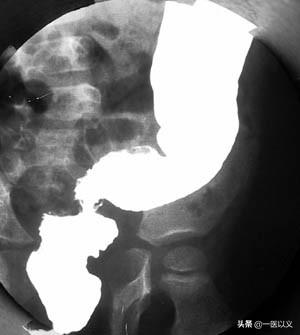

Der Bariumeinlauf spielt eine wichtige Rolle bei der Diagnose von Patienten mit mittelschwerer bis fortgeschrittener Colitis ulcerosa.Es können Ödeme und Ulzerationen der Darmschleimhaut festgestellt werden.

Diagnosekriterien für Colitis ulcerosa: ① Ausschluss von bazillärer Dysenterie, Amöbenkolitis, Schistosomiasis, Darmtuberkulose, Morbus Crohn, Strahlenenteritis und anderen Ursachen für eine Entzündung des Dickdarms; ② typisches klinisches Bild und zumindest endoskopische oder röntgenologische Darstellung der charakteristischen Veränderungen von 1; ③ klinische Symptome sind nicht typisch, aber es gibt eine typische Koloskopie oder Röntgenaufnahme oder Biopsie der Pathologie zur Bestätigung der